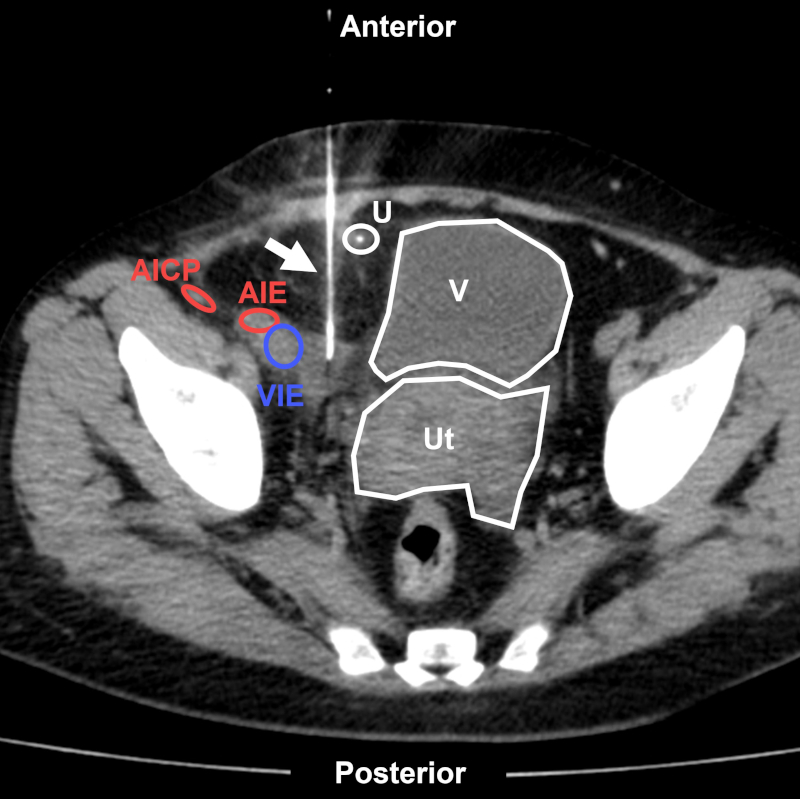

Los accesos para BP pueden ser por vía anterior, lateral o posterior. El abordaje transabdominal anterior (Fig. 17) o lateral (Fig. 18) es útil para alcanzar lesiones ubicadas a nivel paravesical, cadenas ilíacas comunes o imágenes mesentéricas. En caso de utilizar esta vía, se deberá evitar lesionar los vasos epigástricos inferiores, la arteria ilíaca circunfleja profunda, los vasos ilíacos y los órganos de la pelvis1,29.

Figura 17

Mujer de 44 años con colección infrarrenal postrasplante renal derecho. BP transabdominal anterior (flecha) bajo TC. Estructuras a evitar: U: uréter reimplantado; AICP: arteria ilíaca circunfleja posterior; AIE: arteria ilíaca externa; VIE: vena ilíaca externa; V: vejiga; Ut: útero. Aguja utilizada: Chiba 20 G. Diagnóstico final: linfocele posquirúrgico.